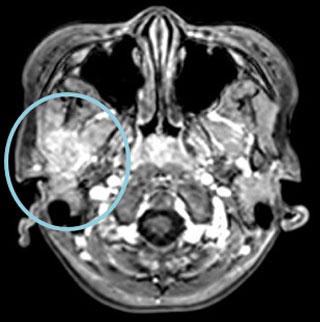

症例:7歳

右下顎骨にLCHの骨再発をきたした。HU内服治療を開始後、溶骨部分の順調な修復が認められた。

MRI T1造影

ハイドロキシウレア開始時